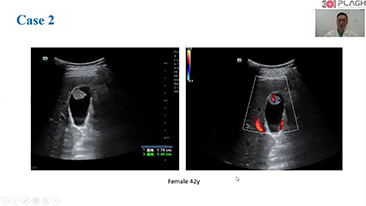

L'ottimizzazione dei flussi di lavoro in ambito ostetrico e ginecologico ├© necessaria per completare grandi volumi di visite di screening per la salute delle donne. Ad esempio, le malformazioni del sistema nervoso centrale (SNC) sono una delle anomalie congenite pi├╣ comuni. A causa di varie circostanze che limitano l'accuratezza delle immagini, come la posizione poco adeguata del feto, l'MSP ├© particolarmente difficile da rilevare tramite l'ecografia 2D. Pertanto, il rilevamento e le misurazioni automatizzate possono migliorare notevolmente l'efficienza della scansione.